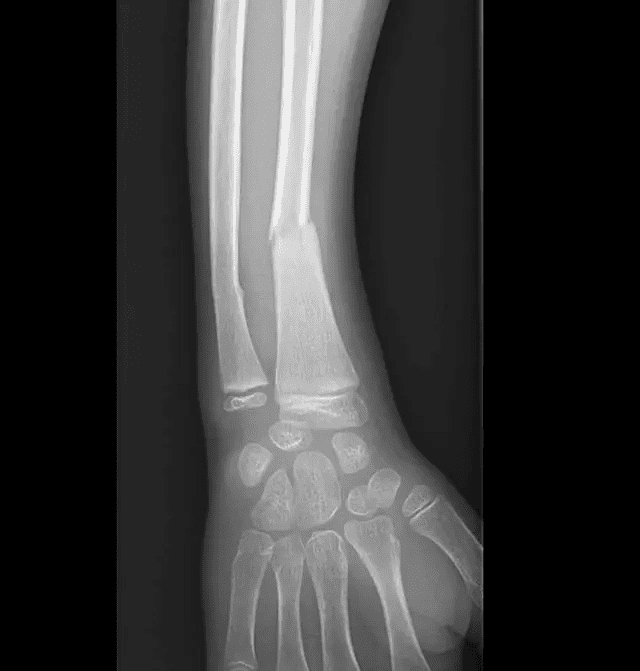

Traumatisme du membre supérieur droit en jouant au football suite à une chute sur la paume de la main.

Radiographie

Radiographie initiale